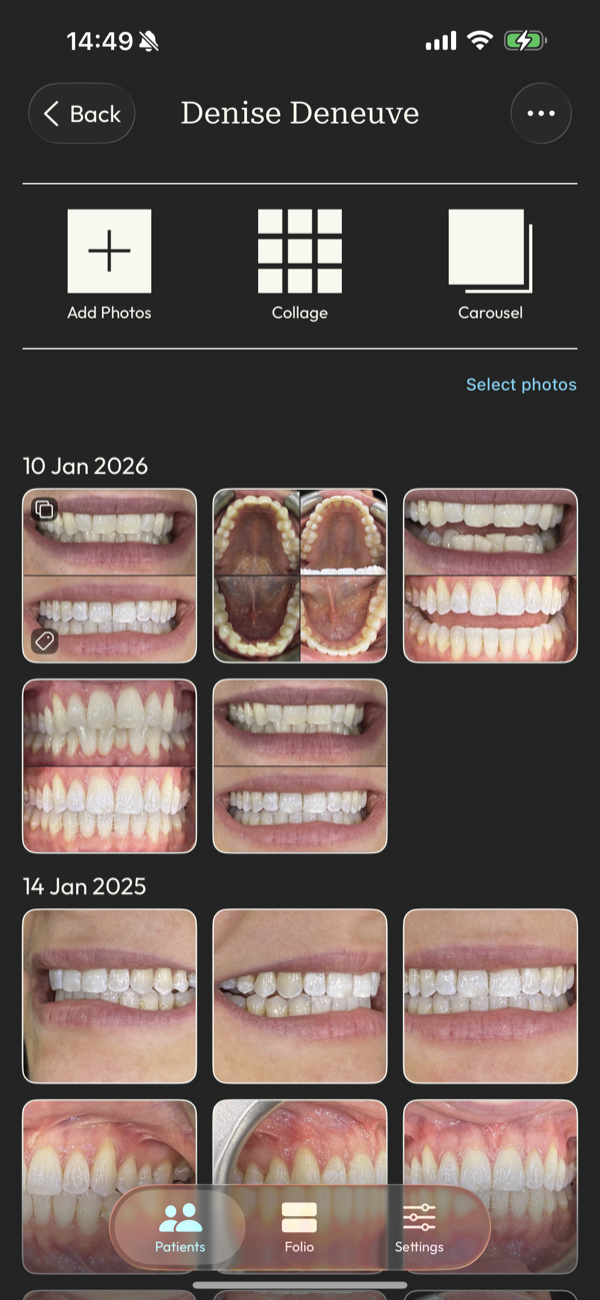

all your photos in one place

Manage your portfolio effortlessly from your phone, and sync with other devices for optimised, up-to-date images, organized by patient and date.

find the right photo in an instant

Give clients confidence and clarity in the moment with intuitive tagging that makes images just a tap away whenever you need them.

DentalFolio is designed around how clinical photography is actually used: by patient, by case, and for clear before-and-after presentation, with consent information kept alongside the images.

The real time sink is finding the right images when they're needed, often just before or during a patient conversation. DentalFolio keeps photos organised by patient and case, removing the need to scroll through unrelated images.

Photos captured in the app are also automatically oriented, reducing small points of friction that add up over time. The result is a calmer chairside experience with fewer interruptions to flow.